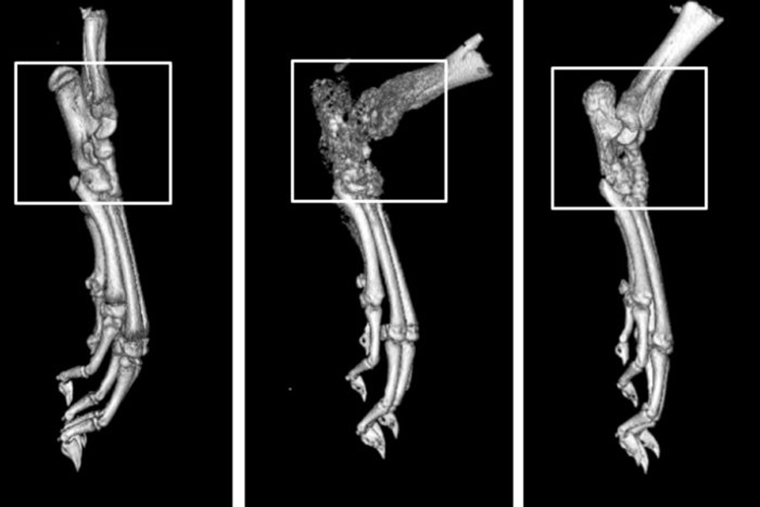

Why chikungunya, other arthritis-causing viruses target joints (Links to an external site)

Chikungunya virus is a growing threat to the United States and other regions of the world as the mosquito that carries the virus expands its reach. Telltale symptoms of chikungunya infection are fever and joint pain that last about a week. But in up to half of patients, the virus can cause a debilitating form […]